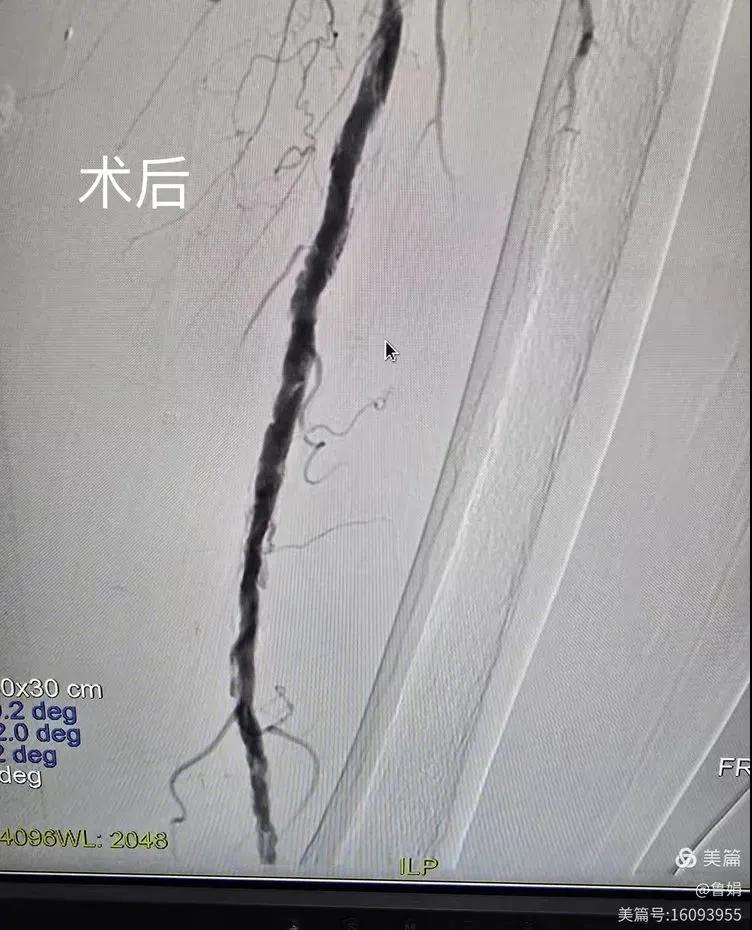

據悉,該患者,女,73歲,下肢動脈硬化閉塞癥,“以靜息痛,間歇性跛行”入院,CTA評估:股淺動脈,腘動脈間斷性多段重度狹窄,外二科血管外科團隊根據患者病情,結合檢查結果,經過科室會診后,決定對該病人行介入治療。手術由周創業副主任與北大一院血管外科專家郭宏杰教授聯合開展,對股淺動脈,腘動脈重度閉塞段行血管開通+藥涂球囊擴張成形,術后狹窄明顯緩解,血流恢復!

下肢動脈閉塞的介入開通是外周介入領域難度最大的技術之一,這項微創介入手術的開展,實現了漯河市中醫院在下肢動脈血管介入治療上零的突破,進一步推動了醫院介入治療技術的發展,讓患者足不出戶就能切實享受到優質的醫療資源,極大方便了患者就醫。(介入中心:魯娟)